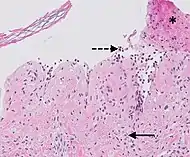

| Prevesicular stage of bullous pemphigoid | Image at right shows influx of inflammatory cells including eosinophils and neutrophils in the dermis (solid arrow) and blister cavity (dashed arrows), and deposition of fibrin (asterisks).[15] However, the diagnosis of bullous pemphigoid consist of at least 2 positive results out of 3 criteria:[19]

|

|

|